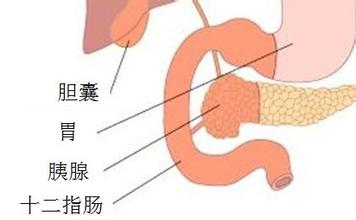

十二指肠球部溃疡的治疗

导读 十二指肠球部溃疡的主要临床表现为上腹部疼痛,可为钝痛、灼痛、胀痛

十二指肠炎的早期症状有哪些?会引发哪些危害

导语 导致十二指肠炎的情况有好多种,主要原因是幽门螺杆菌感染、胃酸过多

十二指肠溃疡有哪些症状,什么病因引起的

导语 十二指肠溃疡是消化科常见病之一,十二指肠任何部位都可发生溃疡,但

如何治疗十二指肠溃疡

导读 十二指肠溃疡是消化科常见病之一,十二指肠任何部位都可发生溃疡,但

十二直肠溃疡的症状

导读 十二指肠溃疡是消化科常见病之一,十二指肠任何部位都可发生溃疡,但 查看更多